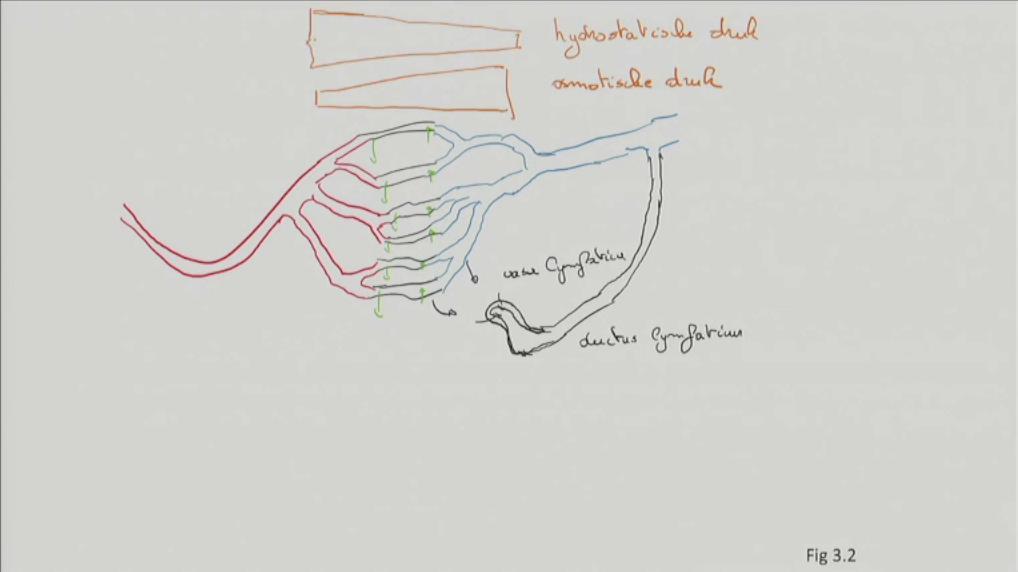

Fig 3.03: Anatomie van de aorta ascendens

A overzicht

vena cava superior (VCS) auricula dextra auricula sinistra apex -

aorta (met klep)

-

tr. pulmonalis

B doorsnede A

atrium dextrum (RA) atrium sinistrum (LA) aorta tr. pulmonalis

C doorsnede B

atrium dextrum (RA) atrium sinistrum (LA) vena cava superior (VCS) aorta tr. pulmonalis